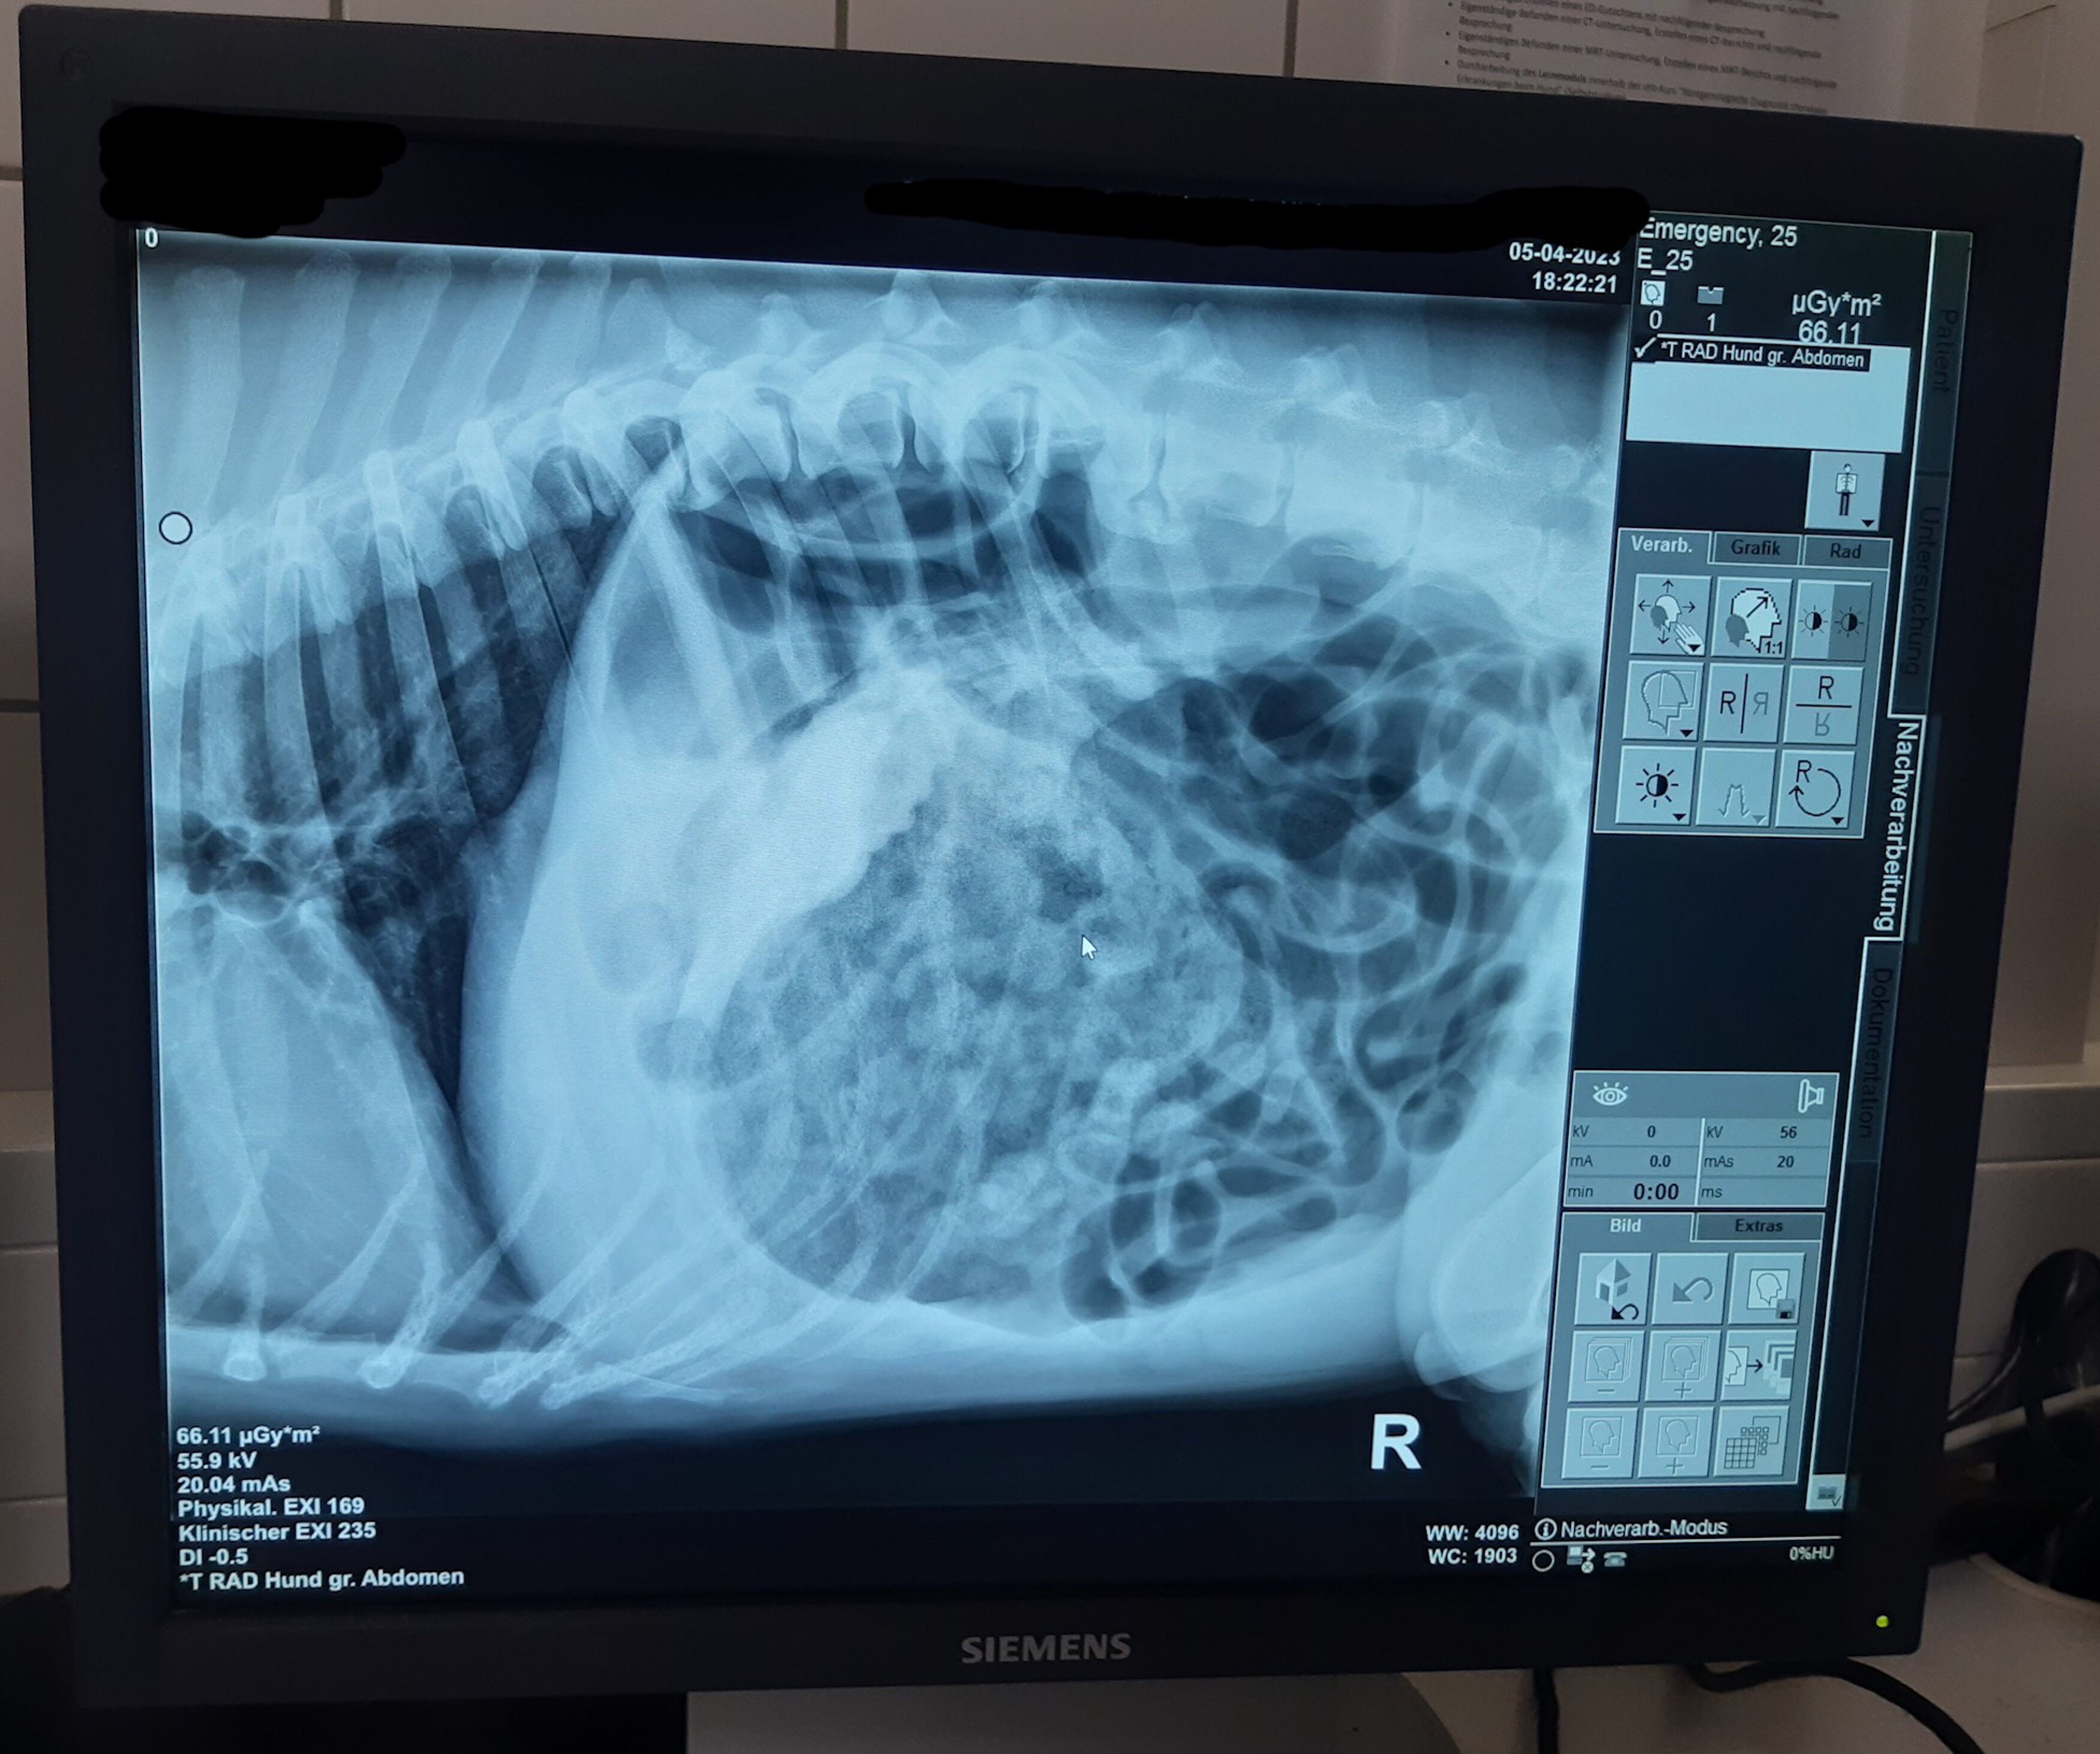

Endlich in der Tierklinik angekommen, wurde sofort ein Röntgenbild angefertigt und unser anfänglicher Verdacht bestätigte sich: Es war eindeutig eine Magendrehung zu erkennen. „Josef“ musste sofort operiert werden, sonst hätte er nicht überlebt. Natürlich stimmten seine Besitzer sofort zu und innerhalb kürzester Zeit war alles bereit für die OP. Nun konnte das Team der Tierrettung nur noch die Daumen drücken. Bei späterer Nachfrage stellte sich jedoch glücklicherweise heraus, dass „Josef“ die OP gut überstanden hatte.